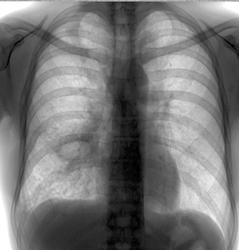

Красиво. Изменения в левой верхушке с моей любимой бронхогенной диссеминацией)

Да похоже, в обеих. И плевральные справа...